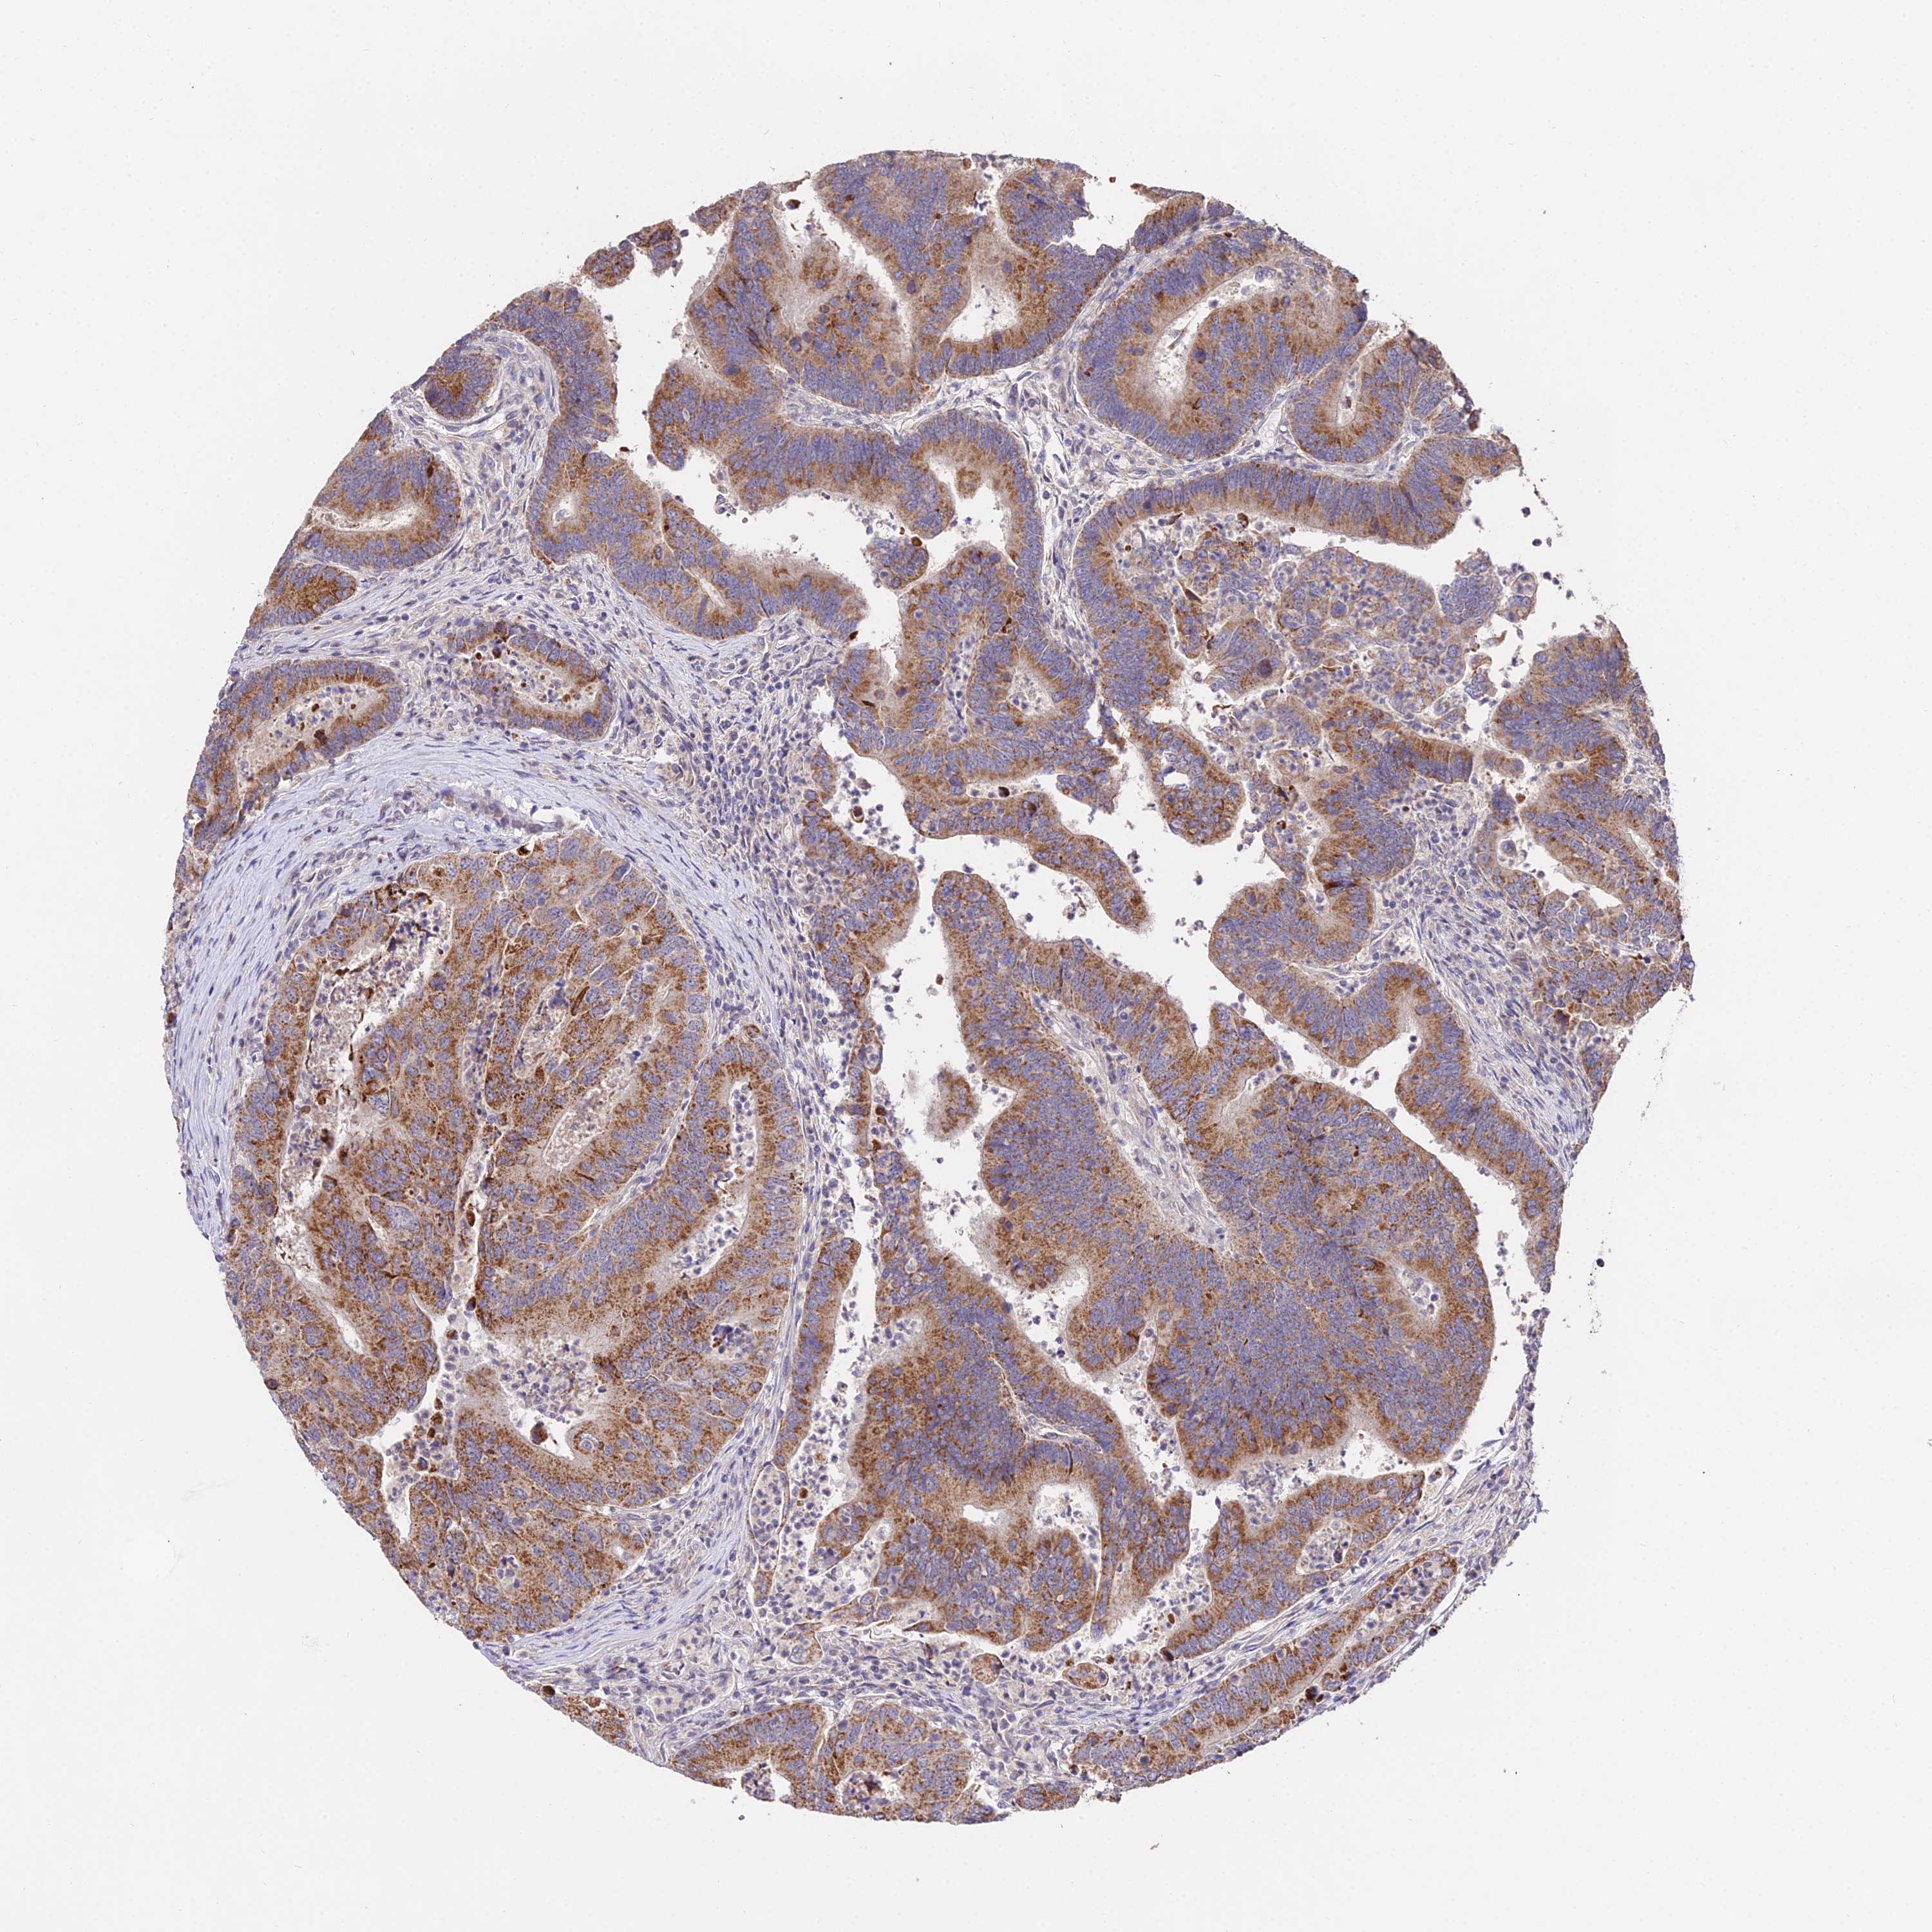

CANCER COLORECTAL CANCER Show tissue menu

Colorectal cancer

Human cancer

Colon adenocarcinoma